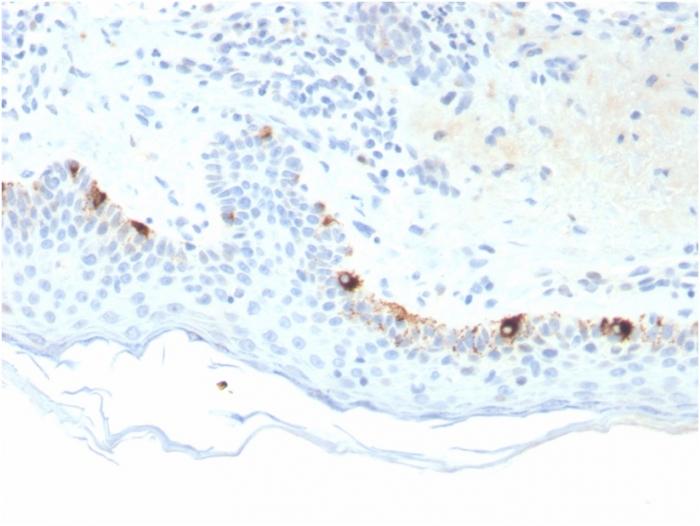

Reacts with a 75 kDa melanocyte-specific gene product, identified as Tyrosinase-related protein-1 (TRP-1). It is involved in melanin synthesis. TRP1 is present on the melanosomal membranes of melanoma, normal melanocytes and nevi. Recent evidence suggests that TRP-1 is involved in maintaining stability of tyrosinase protein and modulating its catalytic activity. TRP-1 is also involved in maintenance of melanosome ultrastructure and affects melanocyte proliferation and cell death. Primary antibodies are available purified, or with a selection of fluorescent CF® Dyes and other labels. CF® Dyes offer exceptional brightness and photostability. Note: Conjugates of blue fluorescent dyes like CF®405S and CF®405M are not recommended for detecting low abundance targets, because blue dyes have lower fluorescence and can give higher non-specific background than other dye colors.

Positive Control

SK-MEL-23, SK-MEL-19, SK-MEL-30, SK-MEL-37 cells. Human Skin or Melanoma.

Melanocytes

Melanoma

IHC (FFPE) (verified)